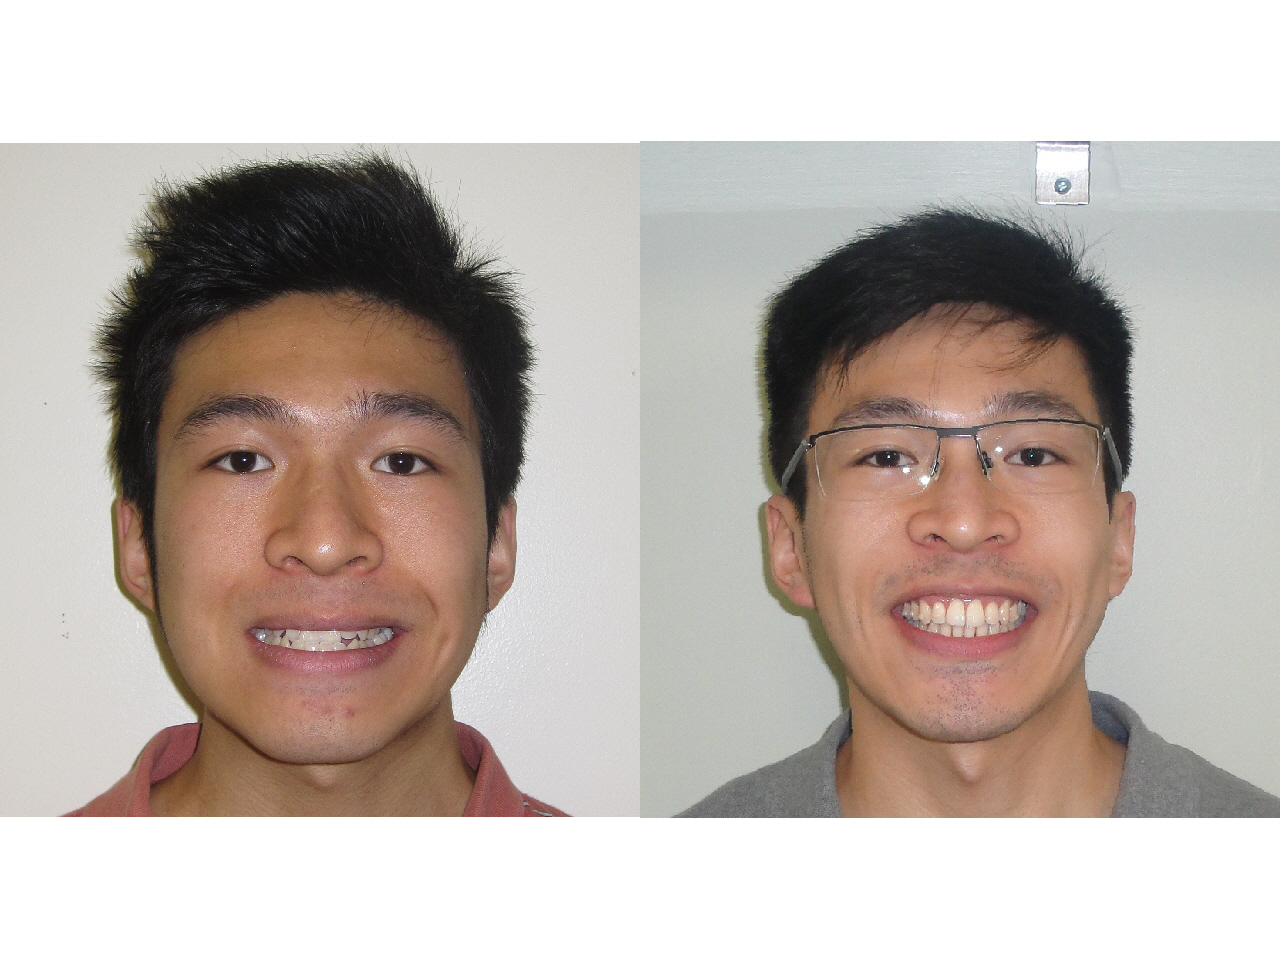

Chris

- Problem: Crowding, Skeletal Underbite

- Treatment: Surgical Orthodontics - Braces with Jaw Surgery

Before and After